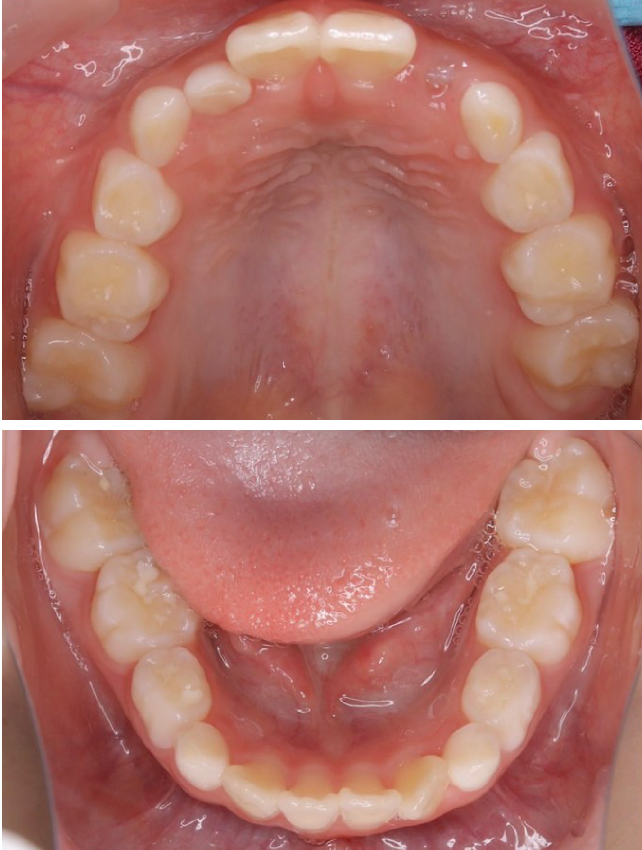

当院の症例

CASE